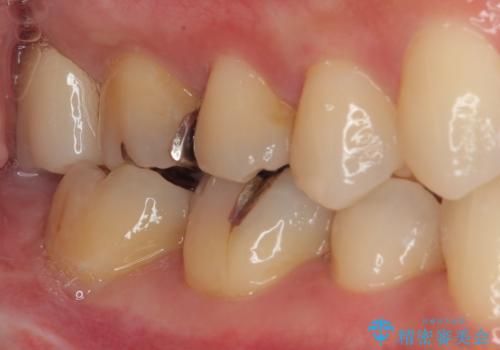

- 元々むし歯があったものの、処置が困難とのことでしたが、矯正治療を終えたので処置をしたいとのことで来院された患者様です。

左右ともに最後臼歯が頬側に顕著に突出しており、むし歯になってしまったことが想像されました。

矯正治療により処置が可能な位置に歯が移動したため、オールセラミッククラウンにて補綴治療を行うこととしました。

歯列が移動したとはいえ、左右ともに後方傾斜しており、むし歯の除去、形成(形を整える)、型取りの全てが非常に困難な処置となりました。